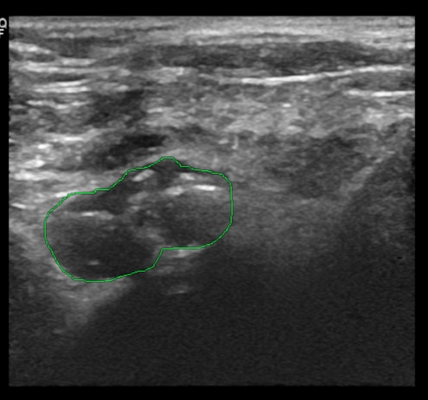

超声显示增生的甲状旁腺,内部可见组织钙化(绿色标记)